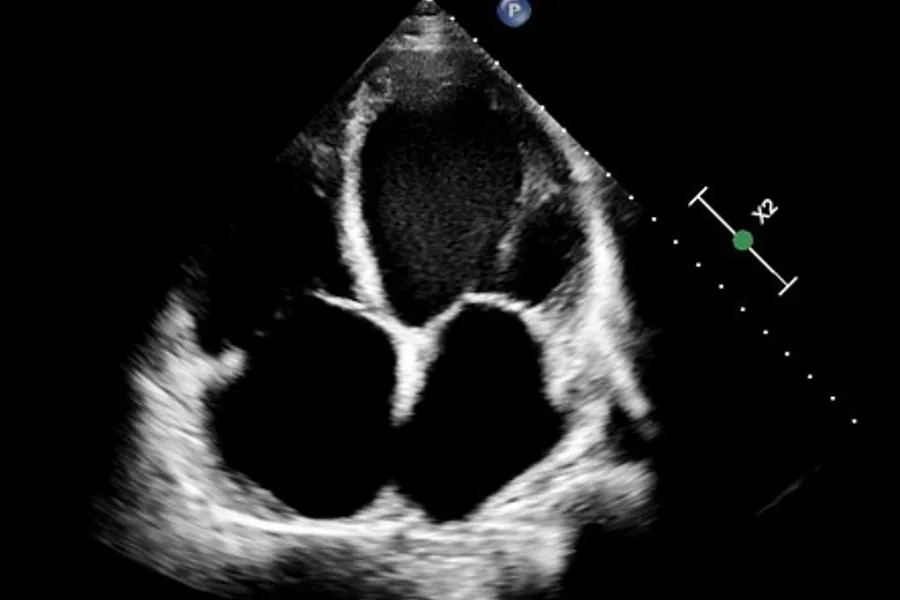

The aim of this research project is to increase knowledge about mutations in the desmoplakin (DSP) gene. Mutations in the desmoplakin (DSP) gene have been associated with arrhythmogenic right ventricular cardiomyopathy (ARVC), which may lead to the development of heart failure and life-threatening cardiac rhythm disturbances. We want to uncover whether physical activity is a risk factors in patients with DSP mutations. In addition, we focuses on patients with dilated cardiomyopathy (DCM), both on how they should be treated, their prognosis and when they should have an implantable cardiac defibrillator (ICD).